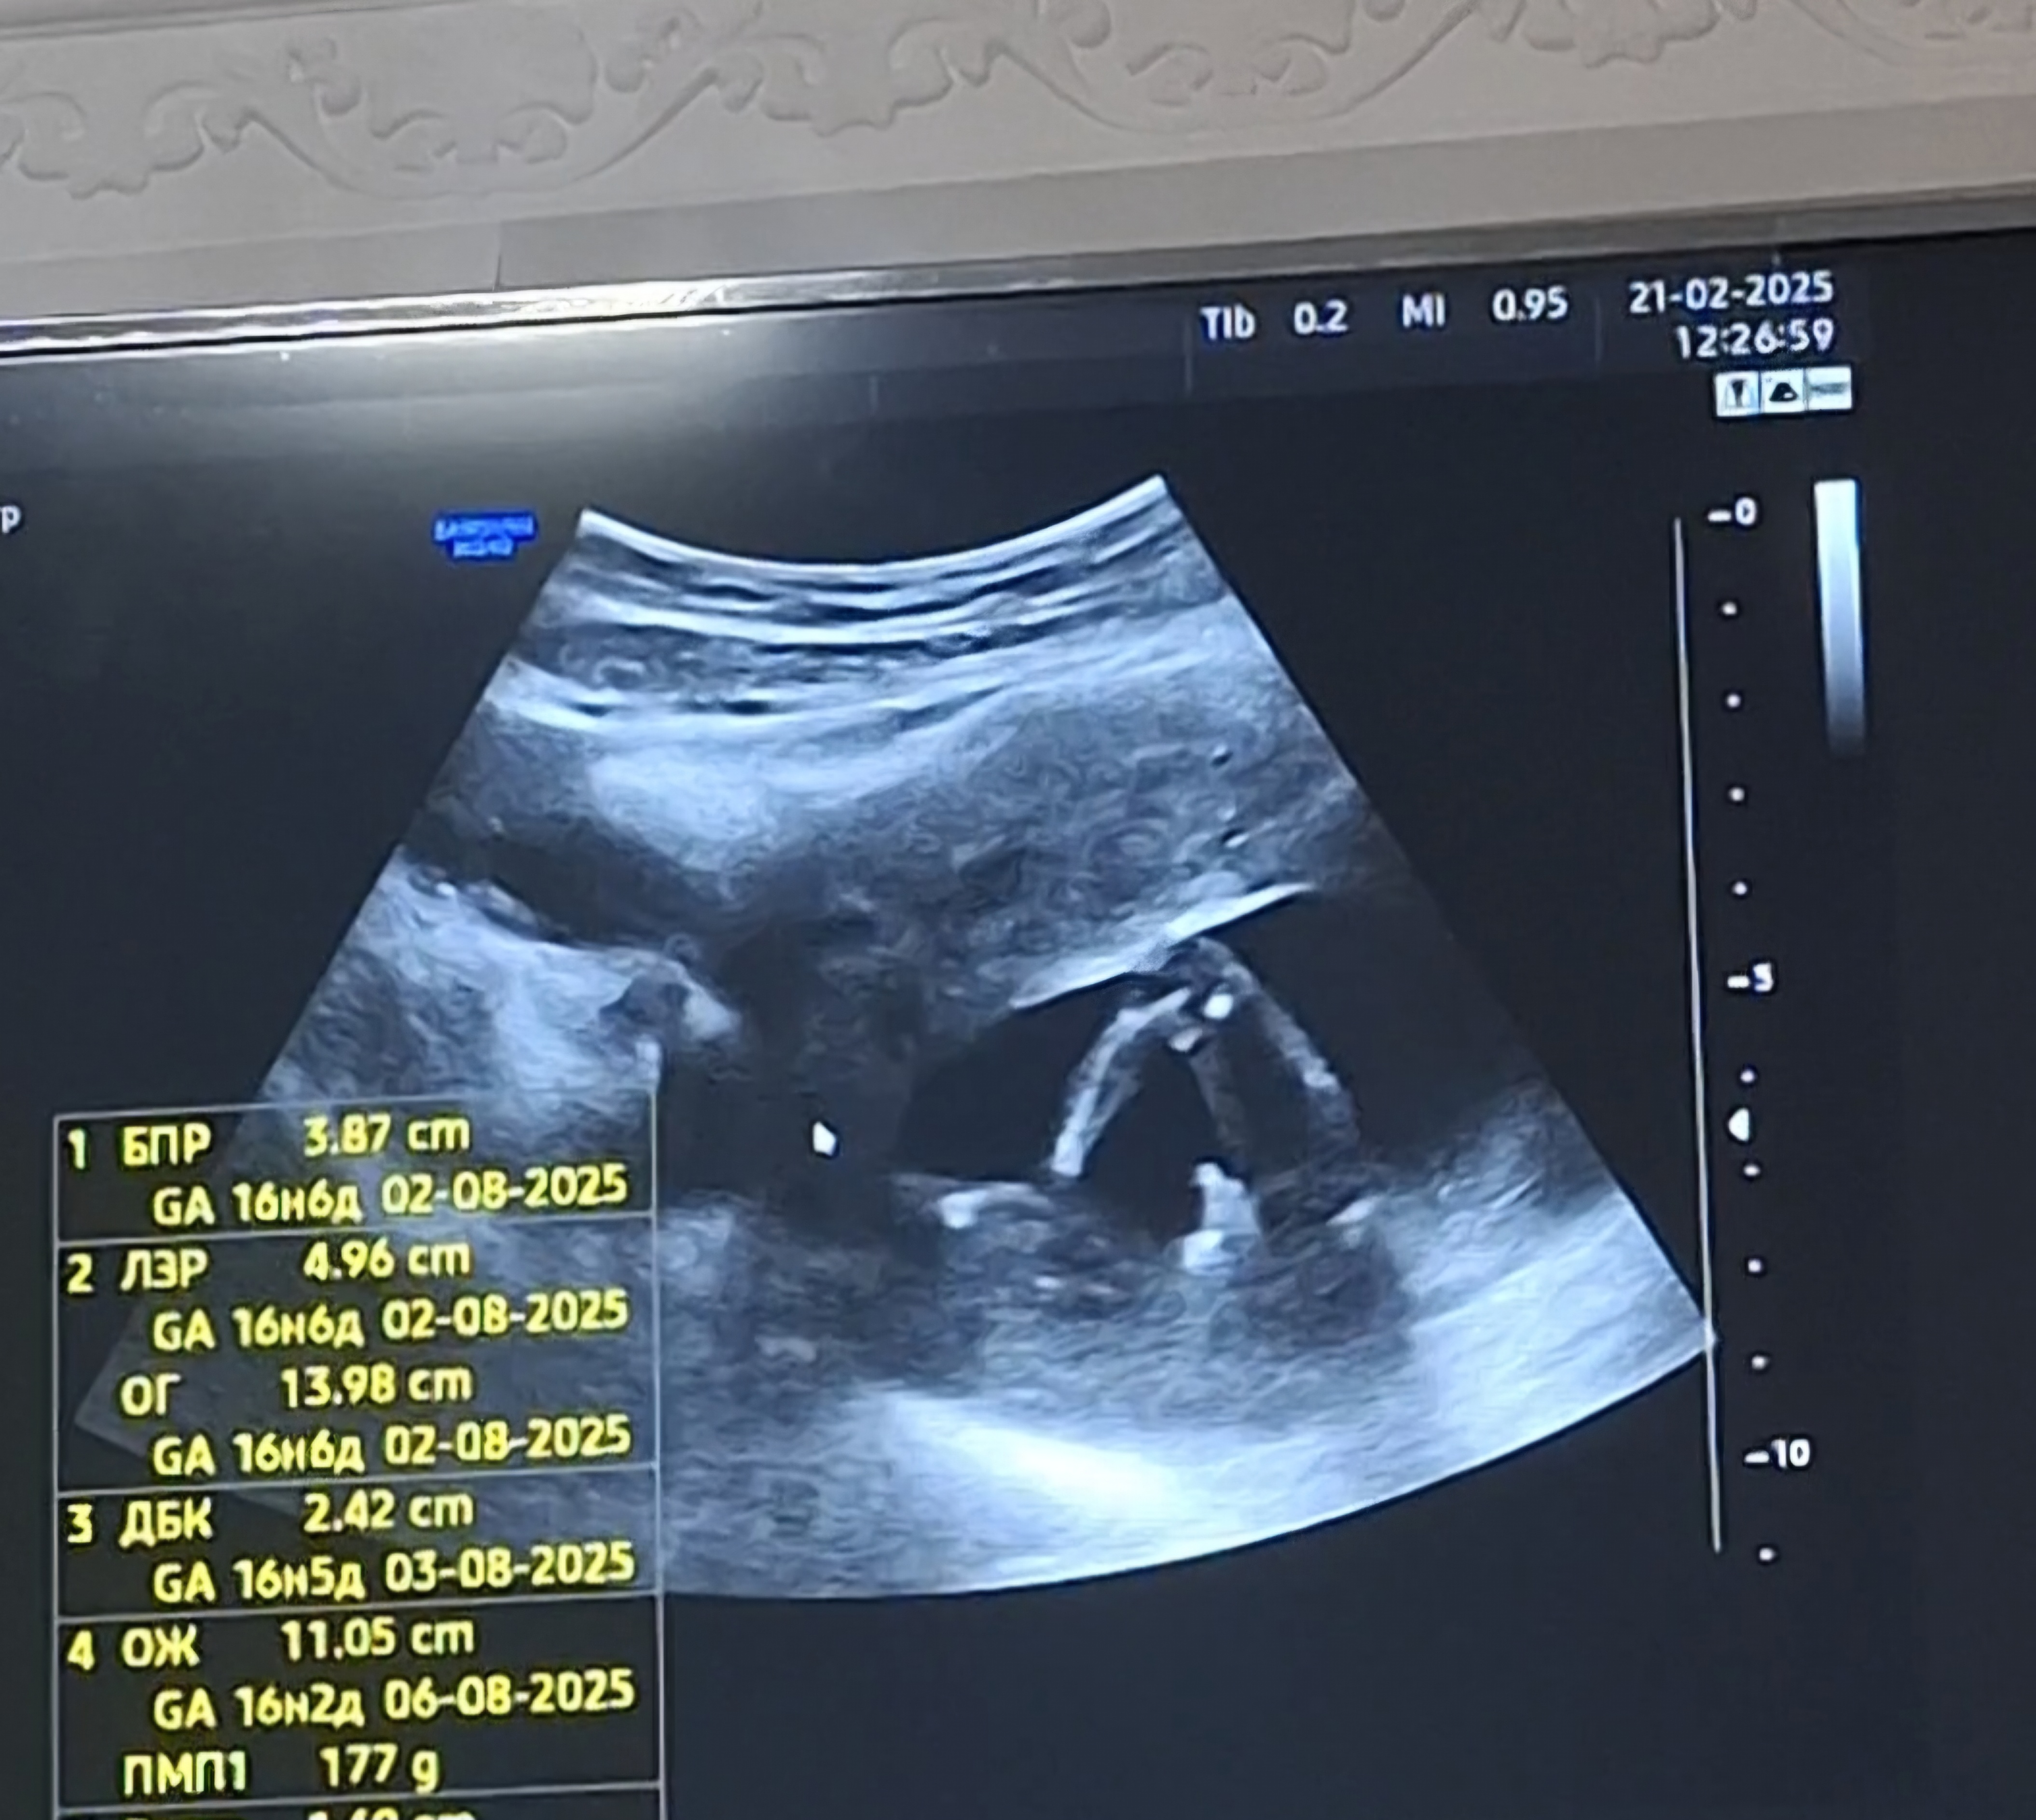

Всем привет была на узи 17 недель ,долго рассматривал пол ребёнка и сказал ДЕВОЧКА, я на радостях хотела сюрприз мужу сделать начала пересматривать видео и теперь сомневаюсь, может ли это быть пуповина?

Как по мне это писюн, у девочек так не торчит...а пуповина имеет другой вид на узи

Лариса , Уже 33 недели, У нас Девочка ) а это была пуповина между ногами